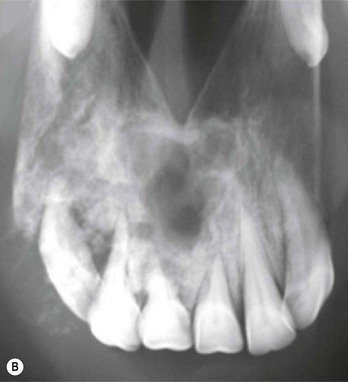

They may be overtly tooth-like, or contain little or no obvious dental tissue. They often develop a central, cystic region and cause bony/solid swellings and abnormalities in the associated dental arcade (Fig. 11.6). Occasionally, they can present with a discharging sinus on the side of the face. Late presentation shows an advanced and aggressively destructive epithelial tumor with extensive bone loss (Fig. 11.7).

Fig. 11.6 (A) Facial swelling caused by an ameloblastoma. The tissue contained no obvious dental tissue remnants. This differentiates it from an ameloblastic odontoma. (B) Radiographic appearance of an ameloblastoma in a 2-year-old Thoroughbred colt showing the characteristic multiloculated nature with radiodense fragments throughout the mass.

Reproduced with the permission of Dr Bruce Bladon.

Biopsy and radiographic findings are typical but can be similar to other tumor masses. Ameloblastomas usually have a rubbery consistency and have a roughly spherical or multilocular shape with a cystic radiographic appearance (Fig. 11.6B). Odontomas are radiolucent or partially mineralized, with foci of calcified tissue mixed throughout. Even when there is extensive ulceration, there should be little confusion between ameloblastomas and carcinomas or sarcomas, which tend to be much more destructive than tumors of dental origin.